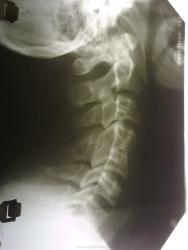

Мне кажется C3 несколько смещен назад.

Уважаемый DOK-A , это не молодой человек, а женщина " бальзаковского" возраста. Действительно С3 смещен.Наверное,появилась клиника, в связи с этим и обратилась.А зачем снимали-это не к нам, а к невропатологам.

Асимметрично расширена щель между передней дугой С1 и "зубом". Мне в таких случаях хочется С1-2 трансорально сделать. В суставной паре С3-4 не полная симметрия, возможно, из-за врожденной конкресценции, а может и травма была. Твердого нёба не видно, но вероятна и базилярная импрессия.